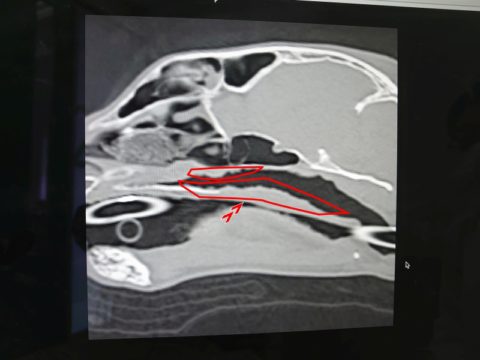

先生からCTと内視鏡の映像を見せてもらった

鼻咽頭内にぼこぼこしたものがへばりついてる..

確かに先日見せてもらったワンちゃんの狭窄とは異なり、空洞は広いようだけど何かがへばりついてる..

先生が言っていた「ぼこぼこしたもの」は、この白いぼこぼこのことだった

鼻咽頭内は膿とか血液とか鼻汁とかはなく、ただぼこぼこしたものが覆い尽くしている..

先生の所見では今のところこれが炎症によるものなのか、リンパ腫なのかは判断できないとのこと..